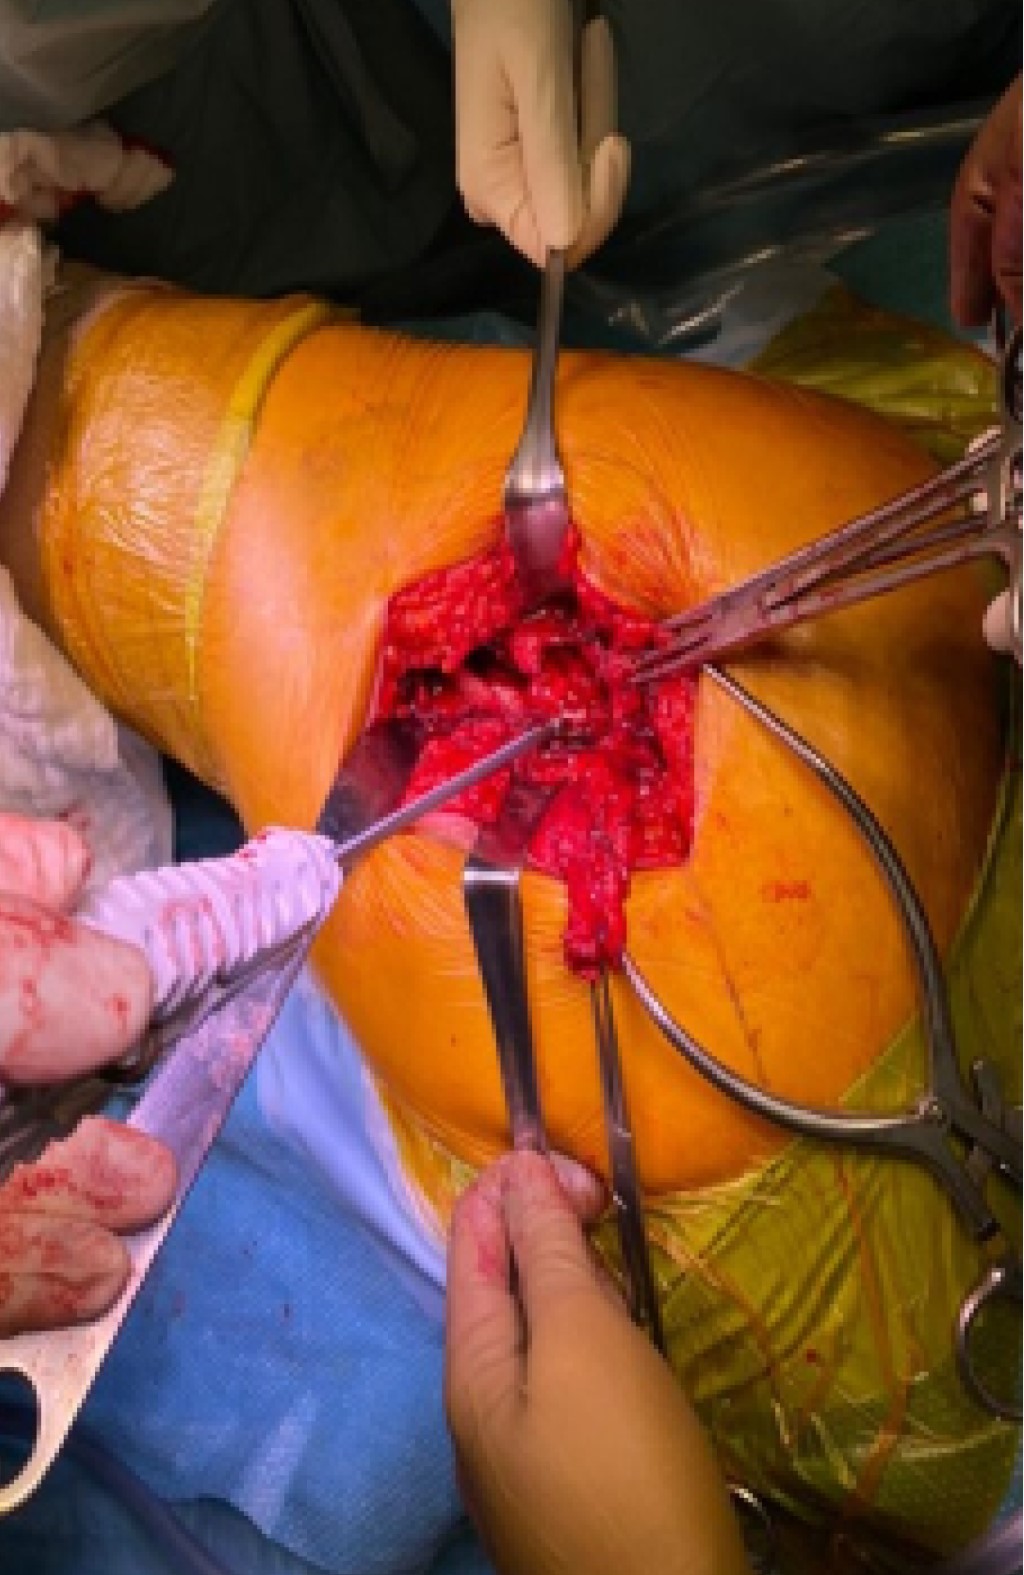

Se optó por una reparación del tendón del glúteo medio con un ancla metálica de 5 mm de doble sutura, realizando pase tendinoso tipo Krakow (Figura 3)­­. Asimismo, se le realizó la transferencia de la porción anterior del músculo glúteo mayor al trocánter mayor, realizando la tenodesis sobre porción lateral femoral decorticada con tres suturas transóseas anteriores y tres posteriores, utilizando puntos simples con tereftalato de etileno del 1 (Ethibond Johnson & Johnson®), dos suturas transóseas distales con extensión proximal tipo Krakow con tereftalato de etileno del 1 (Ethibond Johnson & Johnson®), y reforzamiento de transferencia con anclaje a vasto lateral, utilizando puntos en cruz con poliglactina 910 del 2 (Vicryl Johnson & Johnson®) (Figura 4).

Figura 3

Figura 4